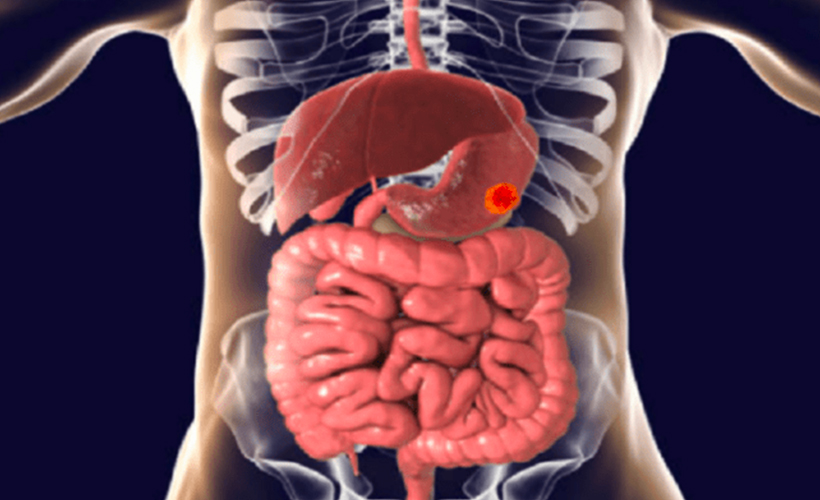

Mide kanseri, midenin iç zarında gelişir. Bu kanser türü genellikle diğer türlere göre daha yavaş büyür ve nispeten hafif semptomların erken aşamalarda gözden kaçması kolaydır.

İlerlemiş mide kanserinin semptomları arasında kusma, mide ağrısı, halsizlik, sık geğirme, sarılık, karında sıvı birikmesi ve yutma güçlüğü sayılabilir.

NHS, mide kanserinin birçok potansiyel semptomu olduğunu, ancak tespit edilmesi zor olabileceğini söyledi.

Ve devam etti: "Mide ekşimesi veya asit reflü, yutma problemleri, hasta hissetme, sık geğirme gibi hazımsızlık semptomları ve yemek yerken çok çabuk tok hissetme gibi sindirim sürecini etkileyebilir."

Mide kanserinin diğer yaygın semptomları arasında bağırsak hareketlerinde kan bulunur. Mide veya astar kanadığında, sıvı vücudun geri kalan atık ürünleriyle birlikte toplanabilir. Dışkı neredeyse siyah kanla görünebilir.